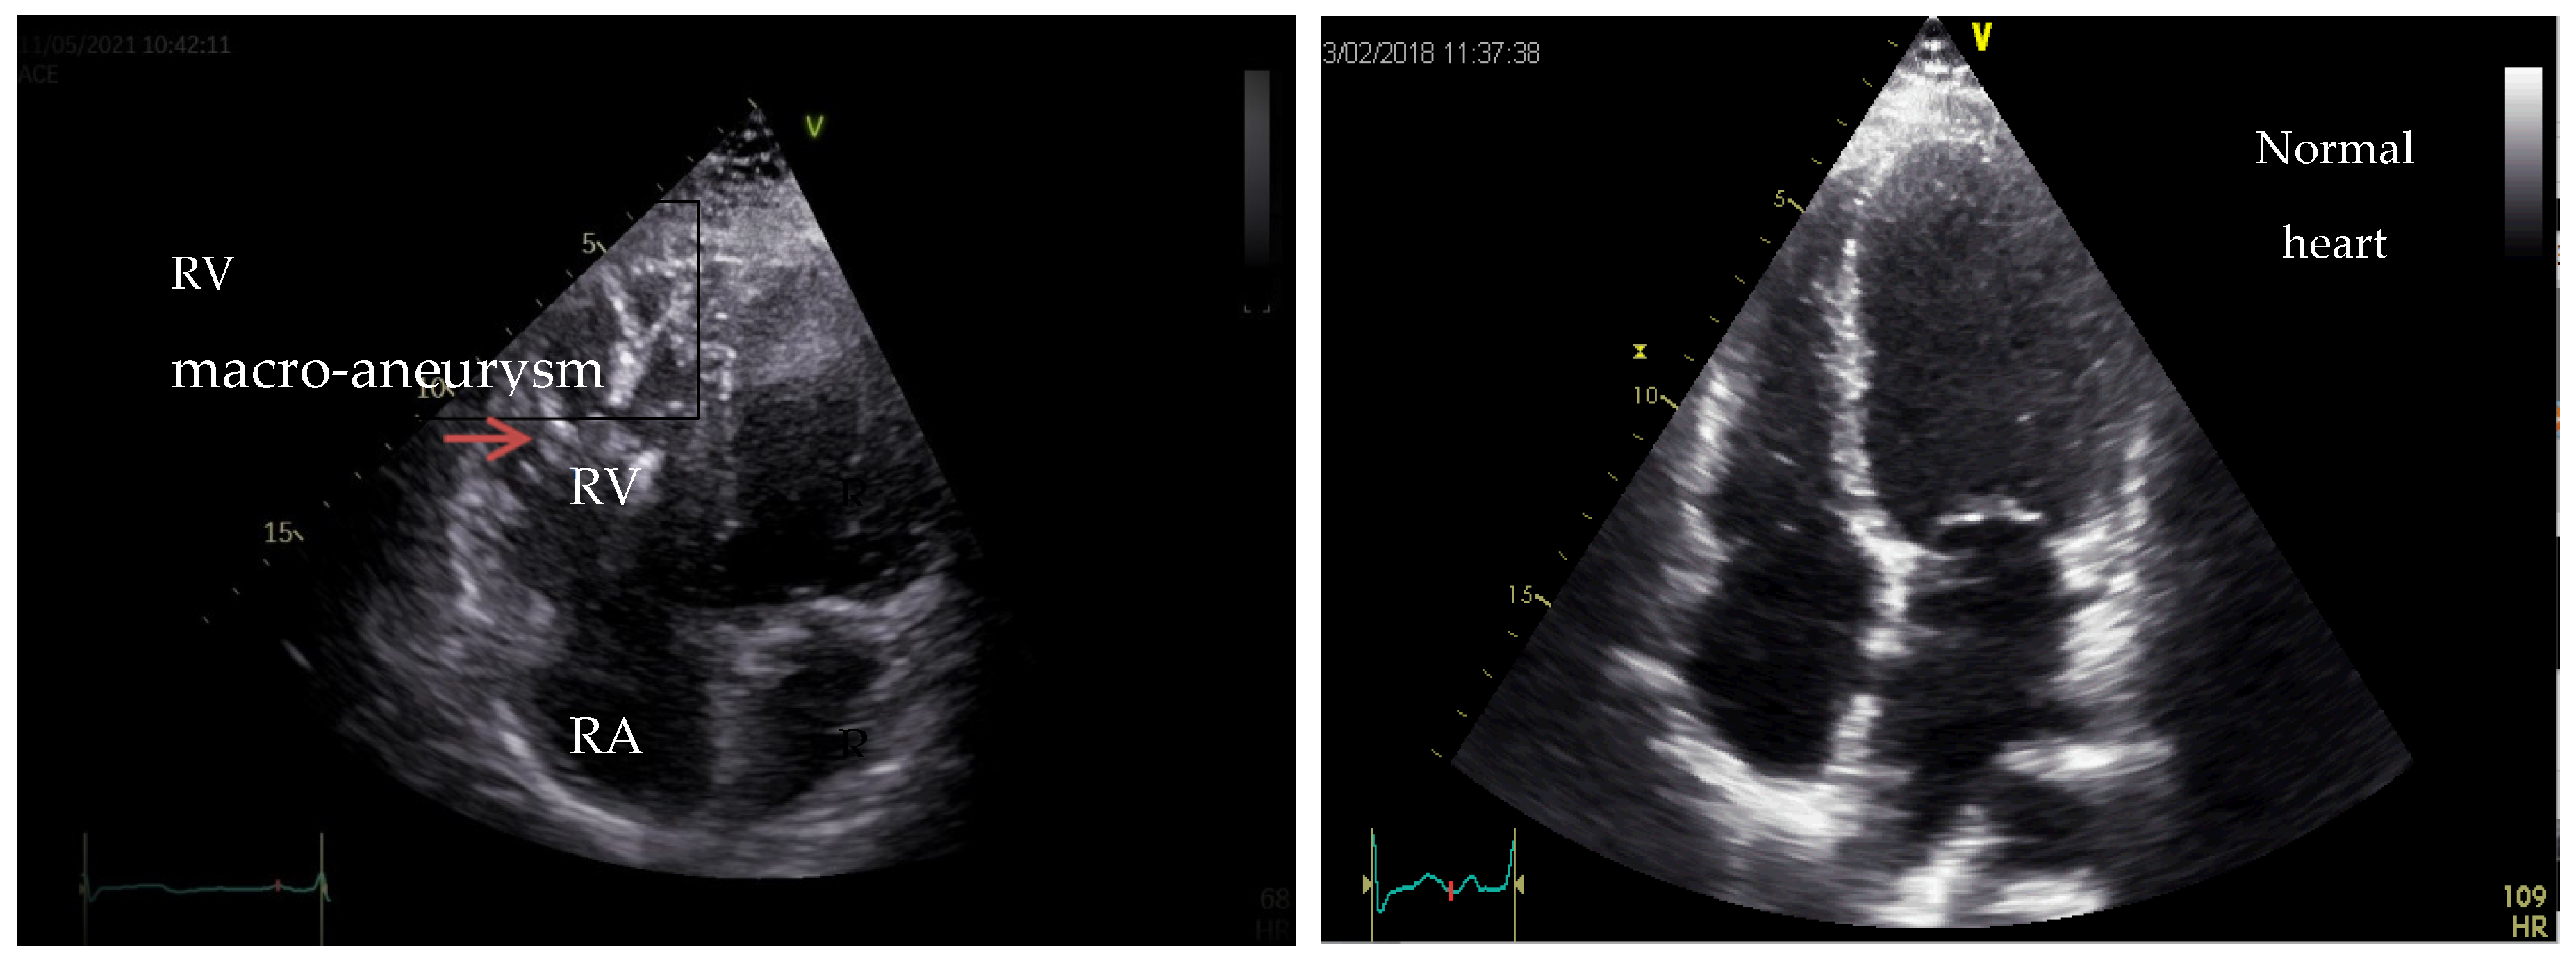

8. Arrhythmogenic Cardiomyopathy (ACM)